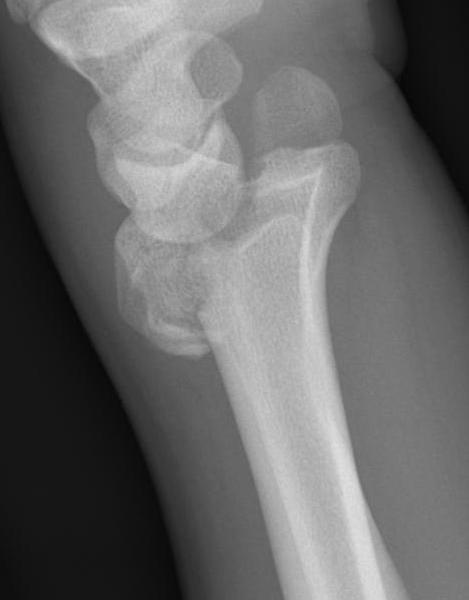

Distal Radius Angles

- radial volar tilt 11°

- radial inclination 22°

- radius is 11 mm longer than ulna

- ulna variance 2mm positive on average